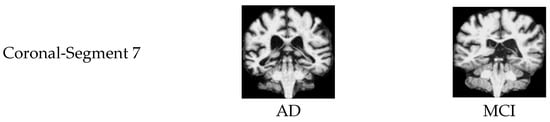

| Segment 7 | 91.2 | 91.1 | 91.1 | 91.1 | 91.3 | 96.2 | |